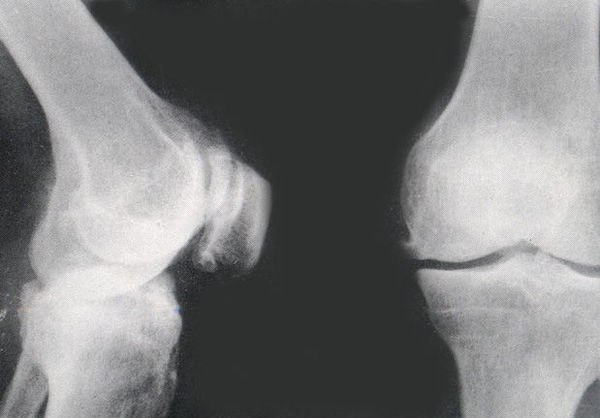

骨刺,是指骨质增生,又称增生性关节炎,中医称“骨痹”、“骨痛”,是常见的慢性关节病。 一说起“骨刺”,不少人的第一印象是“这是老年人的专利。”然而,随着现代生活节奏加快和生活方式改变,骨刺,也就是骨质增生找上了年轻人。

说到骨刺,大家自然会联系到中老年人。然而近年来,由于人们长期使用电脑、看书时坐立姿势不良,青少年患颈椎病几率不断增加。有些青少年(包括运动员)因长时间剧烈的运动,也常被骨刺病痛所困扰。近年来,由于长期坐立姿势不良,青少年长骨刺导致颈椎病的比例大幅增长,骨质增生已成为一种现代疾病。还有一些中青年人,由于长时间上网、开车而不注意保持正确姿势,也加入到骨质增生患者行列中。此外,年龄也是导致骨质增生的主因之一,据统计,55岁以上的中老年人发病率为

60%,70岁以上老年人的发病率达到80%。